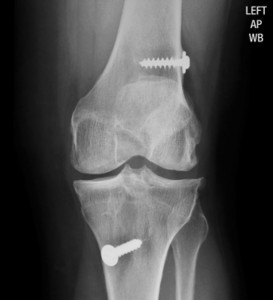

In a typical ACL reconstruction, the torn ACL is removed. Then the type of graft to be used is determined. The most common tendon for the graft is the patellar tendon—which connects the kneecap to the shinbone. About one third the width of the patellar tendon is harvested, along with a plug of bone attached at each end of the graft. The bone plugs are then rounded and smoothed. Holes are drilled in each bone plug to hold the sutures that pull the ligament graft in place. The knee is then prepared to accept the new graft. The intracondylar notch is enlarged, called notchplasty, to eliminate rubbing on the graft. Once this is done, holes are drilled into the tibia and femur. These holes allow the new graft to run between the tibia and femur in the same direction as the actual anterior cruciate ligament. The graft is pulled into place using sutures laced through the drill holes. Screws are put in the drilled holes to hold the bone plugs in place.